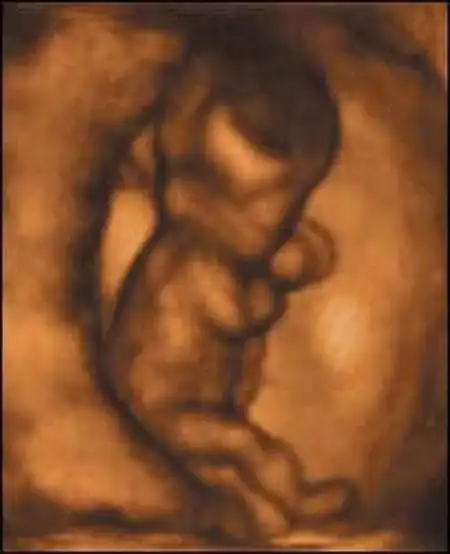

Британские ученые засняли на пленку поведение плода на самых ранних стадиях беременности. Оказывается, зародыш начинает двигаться уже в возрасте 12 недель, вслушивается в голос матери и плачет, когда будущая мама курит...

Уникальная ультразвуковая аппаратура, при помощи которой были получены эти видеозаписи, позволяет не только получать всевозможные фотографии плода, но и наблюдать за ним в реальном времени...

Создатель этой системы профессор Стюарт Кэмпбелл, один из ведущих акушеров Соединенного Королевства, стал знаменитостью в мире медицины благодаря снимкам, на которых зародыш улыбается (раньше считалось, что эта способность появляется лишь после рождения)...

Качество изображений превосходное!...

Специалисты признают, что эти снимки, прежде всего помогающие оценить правильность развития плода, завораживают...

Но главное не это. Главное то, что доктор Кэмпбелл доказал, что "настоящим человеком" эмбрион становится уже в 10-11 недель...

Книга профессора потрясла ученых. В частности, в ней ученый утверждает, что ребенок шевелится уже в 12 недель, задолго до того, как мать начинает ощущать его движения...